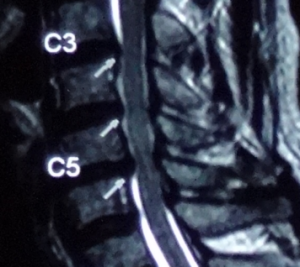

頸椎椎間盤最常見受壓的頸椎關節是頸椎第5節和第6節(C5,6),一般從X光片中可看見椎節之間的空隙變少,椎骨有退化跡象。除頸椎第5節和第6節之外,還有頸椎第3節和第4節(C3,4),亦是受壓較大的部位,而受壓對其他椎節的變化,亦隨之而來。

每節頸椎間盤突出的反射痛及麻痺可分佈於手部不同的位置(圖一)。要分辨椎間盤突出的所在,一定要詳細檢查手部肌力的狀況,進行反射神經測試,並配合病人的徵狀,才能確診。不能單單只靠磁力共震(MRI)得出的報告而作出非必要性的手術治療。磁力共震是幫助醫生確診,並不是幫助醫生來斷症。

除頸椎第5節和第6節之外,還有頸椎第3節和第4節(C3,4),亦是受壓較大的部位,而受壓對其他椎節的變化,亦隨之而來。